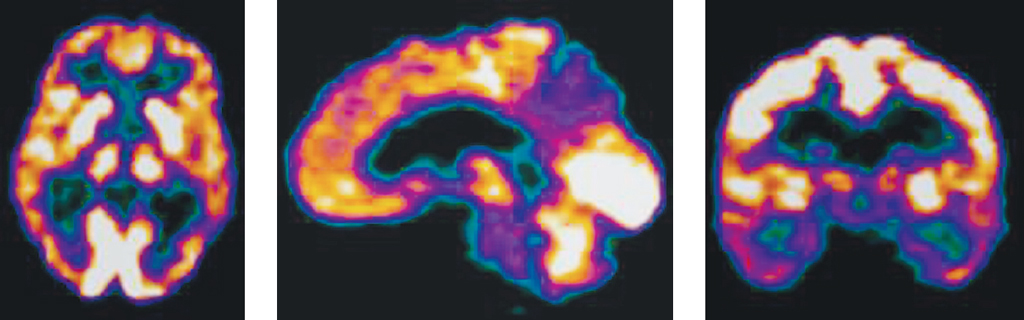

Decreased metabolic activity in the anterior cingulate gyrus was only observed in severe Alzheimer-type dementia, accompanied by hypometabolism in the occipital cortex, indicating further progression of neurodegeneration (Figure 2).

Fig. 2. Alzheimer’s disease, severe dementia: pronounced metabolic disorders in the parietal, temporal lobes, hippocampus on both sides, anterior and posterior cingulate gyrus

Рис. 2. БА, тяжелая деменция: выраженное нарушение метаболизма в теменных, височных долях, гиппокампах с обеих сторон, переднем и заднем отделах поясной извилины

Thus, steady progression of neurodegeneration in AD patients causes a further bilateral decrease in parietotemporal cortex metabolism, a decrease in metabolic activity in the posterior cingulate gyrus, and the formation of new hypometabolism areas (anterior cingulate gyrus, frontal cortex, and occipital cortex) [14].